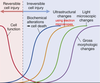

Reversible cell injury

injury during the decline of cell function

Irreversible cell injury

injury during incline of biochemical alterations (cell death), ultrastructural changes, light microscopic changes, and gross morphologic changes